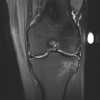

These findings, combined with clinical symptoms, lead to MRI for a definitive diagnosis. MRI of the bilateral knee was performed, revealing a thickened and disc-shaped lateral meniscus consistent with a complete discoid meniscus. There was evidence of a meniscal tear and associated mild chondral changes [5] (Fig. 2).

MRI is essential for diagnosing discoid meniscus, as it provides detailed images of meniscal morphology and associated pathology. In this case, MRI was crucial for identifying the complete discoid meniscus and the associated tear, guiding the surgical approach [5,7]